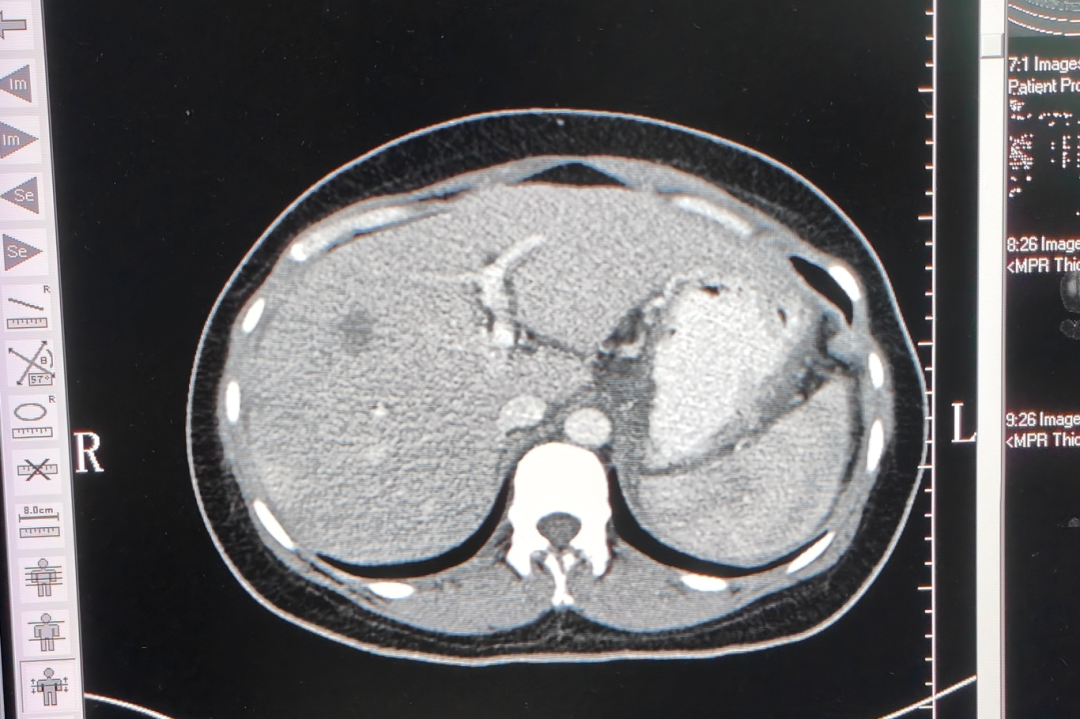

入院时,小向的身体状况并不好,贫血、白细胞红细胞偏低、吃不下东西,还时不时抱着个盆呕吐……影像结果提示,其肝内有多枚实质占位,较大的约7.6×5.2cm;肝门区及上腹部腹膜后可见多处实质占位,最大切面范围约15.8×13.2×10.1cm;而胃底贲门区-腹膜后-胰腺体尾部有巨大不规则软组织密度肿块影,范围约13.1×9.5×9.3cm。

▲2022年6月,治疗前影像检查结果